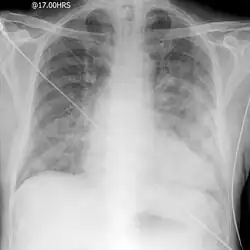

AP portable CXR of a patient in acute pulmonary edema.